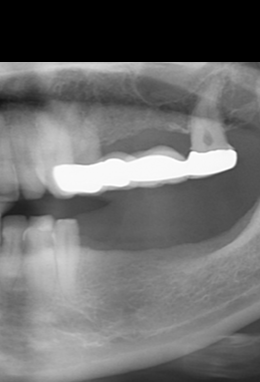

Colocación de implantes en posiciones 35i y 37i, con colocación simultánea de injerto de tejido conectivo.